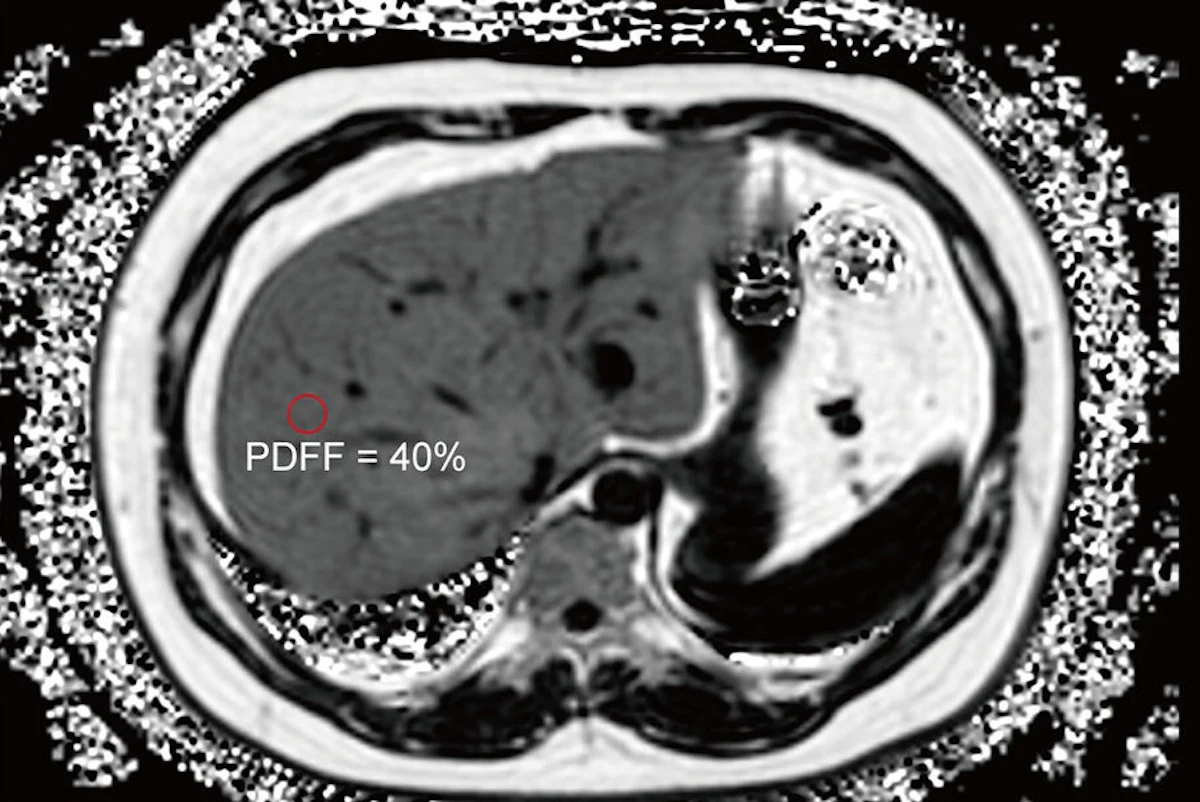

Une étude menée par des chercheurs de l’Université de Wuhan, en Chine, et publiée le 21 octobre dans la revue Radiologie, a analysé les données de 683 patients adultes obèses. L’objectif était d’évaluer la relation entre la quantité de graisse présente dans le foie, quantifiée par la fraction grasse de la densité protonique (PDFF) mesurée par IRM, et le risque de développer un prédiabète ou un diabète de type 2.

Si le PDFF basé sur l’IRM est déjà un outil reconnu pour le diagnostic de la stéatose hépatique, son potentiel dans la prédiction de la dysglycémie chez les personnes obèses restait jusqu’alors moins exploré. L’étude, qui a classé les patients en fonction de leur tolérance au glucose (normale, prédiabète, diabète de type 2) et de la gravité de leur stéatose hépatique (PDFF < 5 %, 5 % à < 15 %, 15 % à < 25 %, ou ≥ 25 %), vient combler cette lacune.